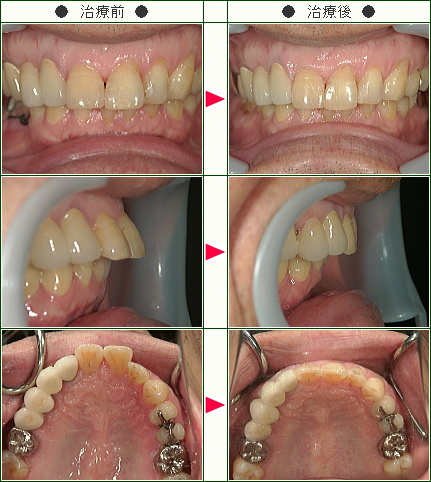

「納得のいくまでカウンセリングをして下さり治療方法も丁寧に説明してくださいました」K.Y様 50歳 女性

子供の矯正が終わったところで幼いころからずっと気になっていた自分の歯の矯正を受けることにしました。

50歳を目前にして不安でいっぱいでしたが、クリニックに行くと納得のいくまでカウンセリングをして下さり、治療方法もひとつひとつ丁寧に説明してくださいました。

全てが心地よく満足しております。

ひとつだけ後悔があるとすればもう少し早くこちらに来ていれば良かったということだけです。

歯並びは第一印象を大きく左右するもののひとつですので、悩んでいる方がいらしたら、ぜひ一日も早くこちらのクリニックにいらっしゃるようおすすめ致します。